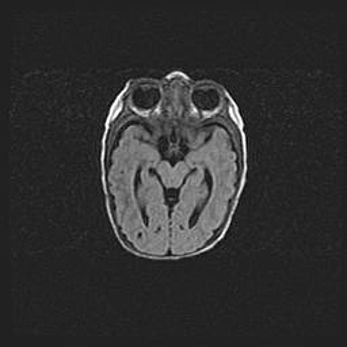

Множественные кисты обоих полушарий головного мозга, наибольшая из них в правой затылочной области. Ассиметричная атрофическая гидроцефалия.

Возраст: 7 месяцев

Вес: 5660 г

Пол: мужской

Окружность головы: 41,5 см

Срок гестации: 28-29 недель

Кисты головного мозга развиваются в результате многоочаговых некрозов вещества мозга и возникают вследствие перенесенной перинатальной инфекции, менингитов, энцефалитов, асфиксии, родовой травмы, расстройств мозгового кровообращения различного генеза. Образованию кист в веществе головного мозга плодов и новорожденных способствуют такие факторы, как высокое содержание в нем воды, недостаточная (или отсутствие) миелинизация и слабая астроглиальная реакция на повреждение.

Кисты могут сочетаться с гидроцефалией и другими поражениями головного мозга.